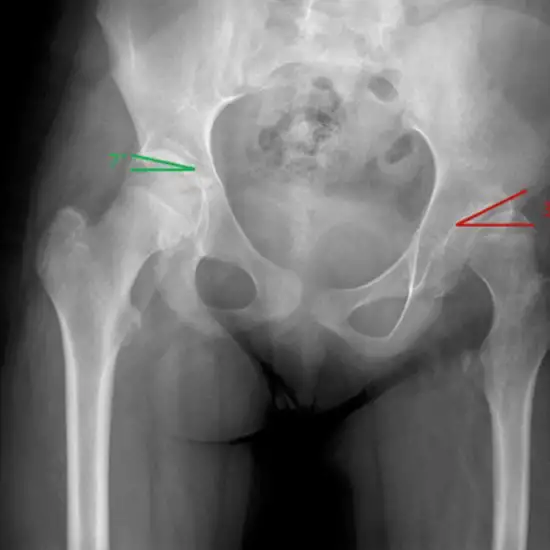

The Left upper femur-hip x-ray AP View shows the femur and pelvis from the hips' front. This X-ray can detect hip fractures and dislocations.

Your doctor may recommend an X-ray of the left upper femur of the hip after an accident, fracture, or significant hip discomfort, groin pain, limp, edema, or deformity.

• To diagnose hip and femur fractures and monitor healing following setting.

• To detect infection, osteoporosis, malformations, or abnormal bone growth.

• To diagnose hip dislocation.